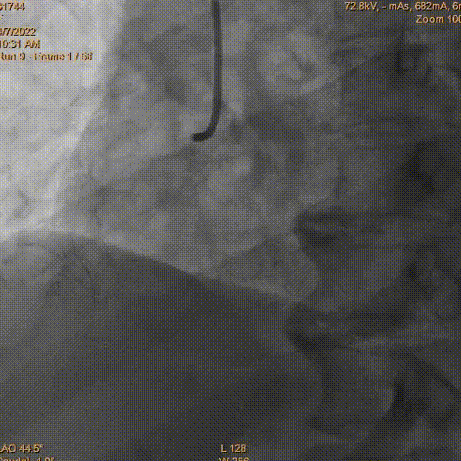

预扩球囊送入困难,通过迂曲血管段轻度受阻,为减少药物球囊释放时间,增加手术成功率,送入Telescope™导引延长导管,然后沿导引延长导管快速送入2.75×16mm药物球囊至病变处。

2.75×16mm Vesselin药物球囊

以12atm×40s充分扩张